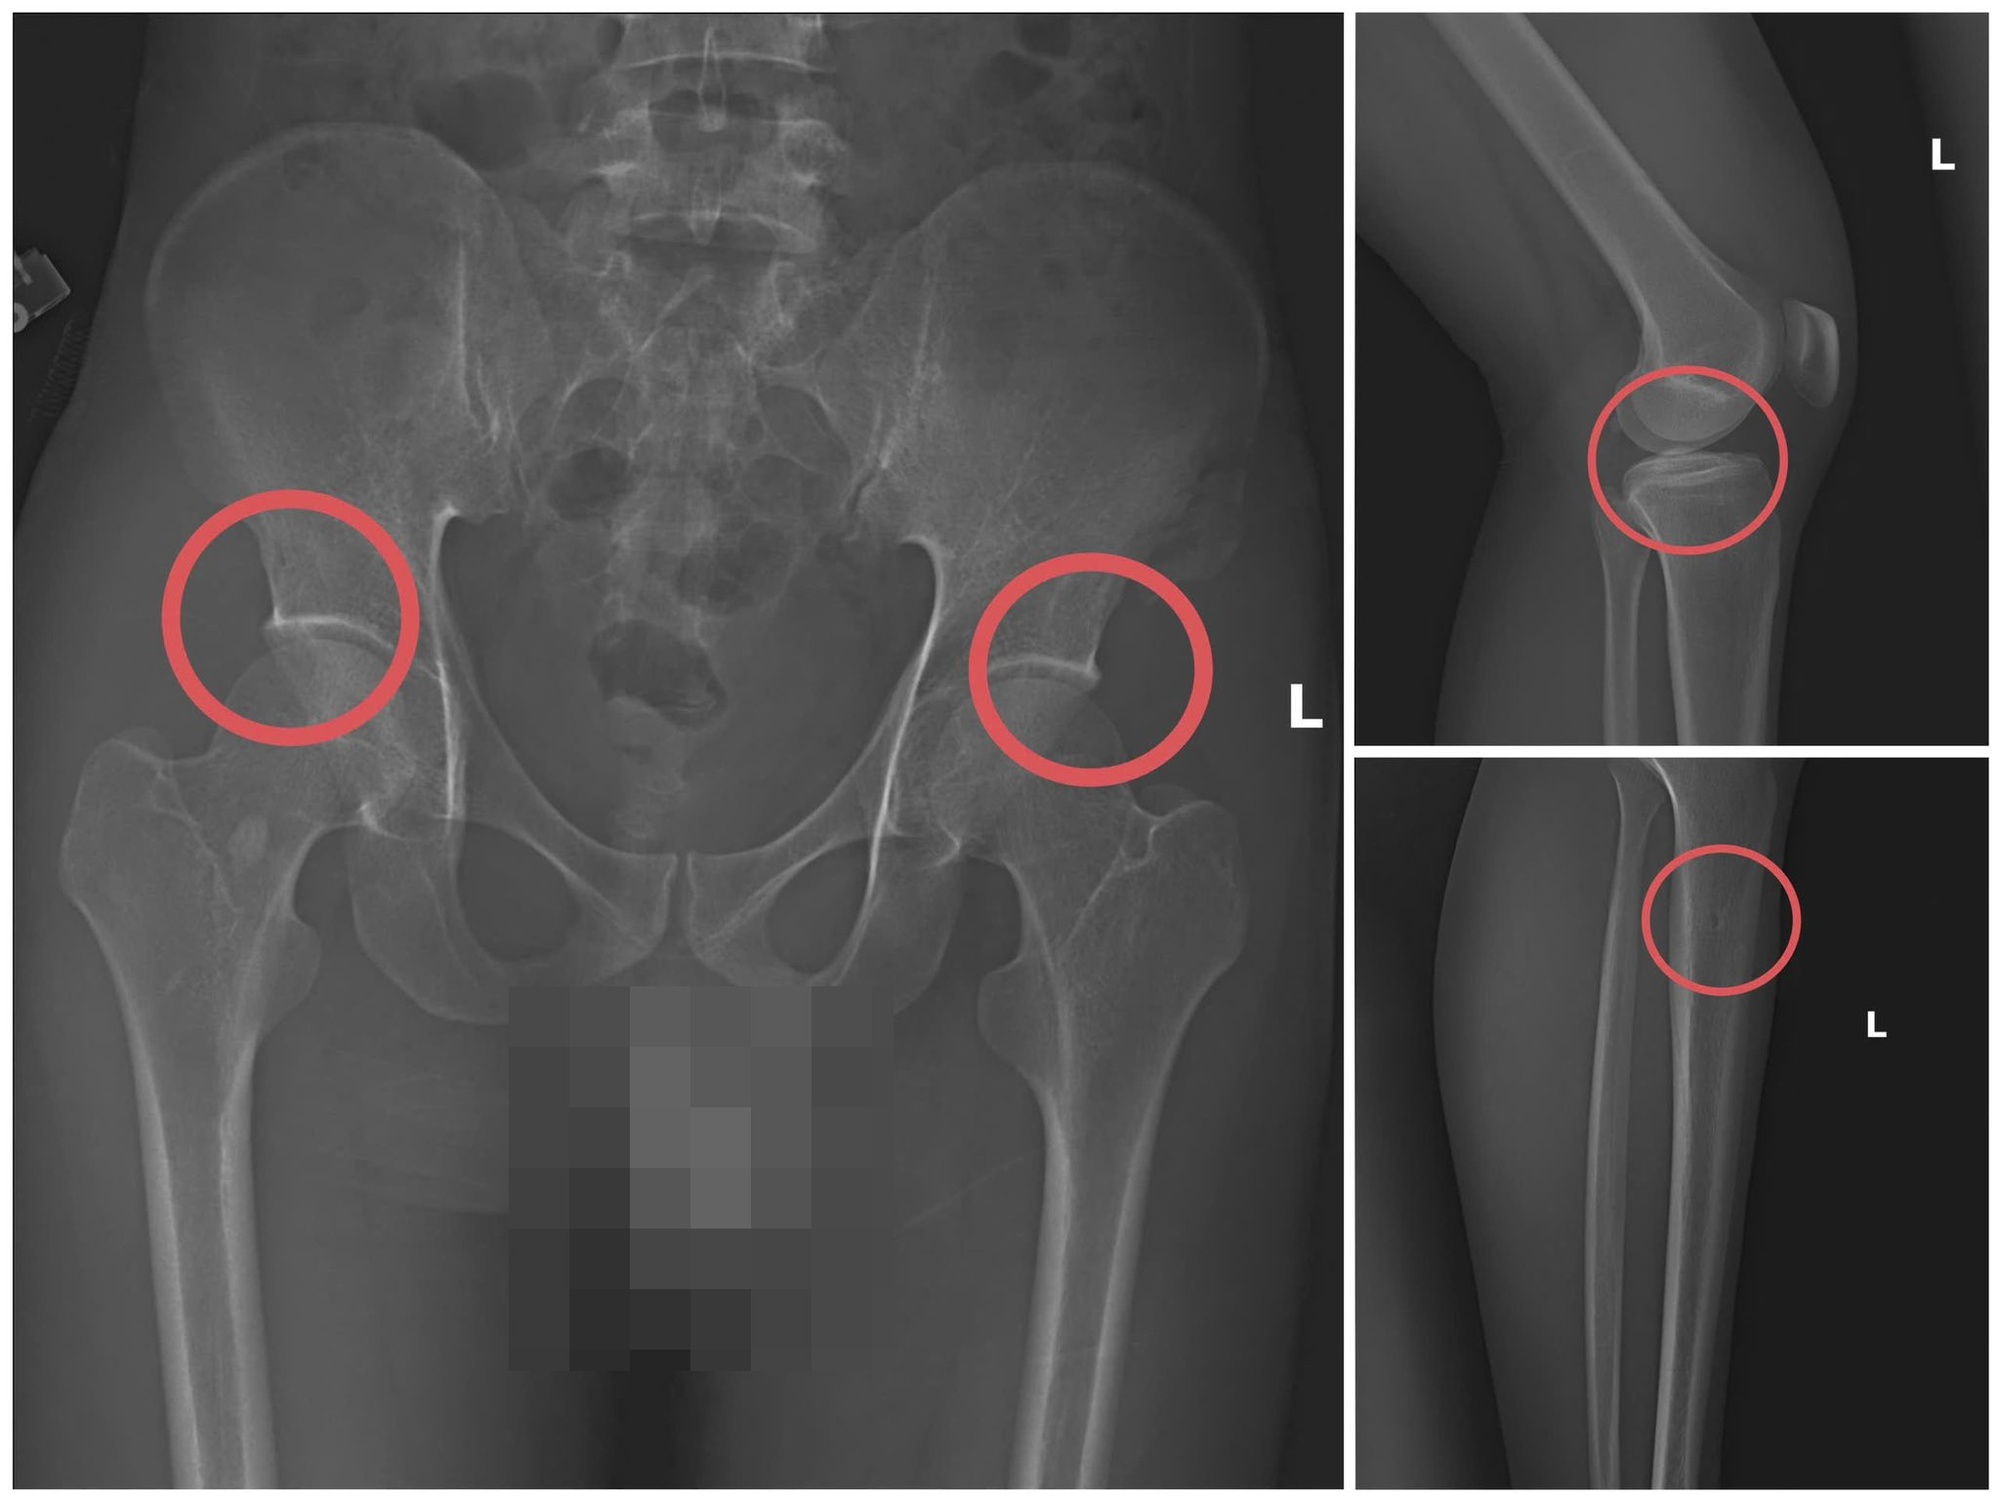

Hình ảnh xương khớp do Châu gây thương tích để chiếm đoạt tiền bảo hiểm nhân thọ – Ảnh: Công an tỉnh Phú Thọ